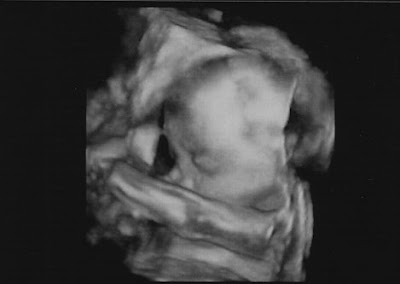

As a surprise we were shown 3D images. The sonographer was trying to be nice and get us a good face shot and Zakumi chose not to cooperate. At first with one fist in front of the face, then with two. There was a lot of tapping on my belly, and each time my babe waved fist like (s)he was getting ready for a fight. Scrappy little baby, like a Pikey from the movie Snatch.

Finally the sonographer backed off and we were able to see some face.